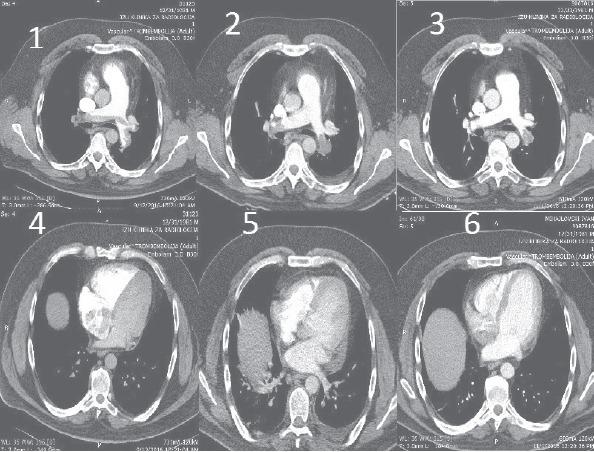

Can rivaroxaban be a drug of choice for treating heparin-induced thrombocytopenia in a patient with pulmonary thromboembolism?

Anatol J Cardiol. 2017 Jul;18(1):77-79. doi: 10.14744/AnatolJCardiol.2017.7805.